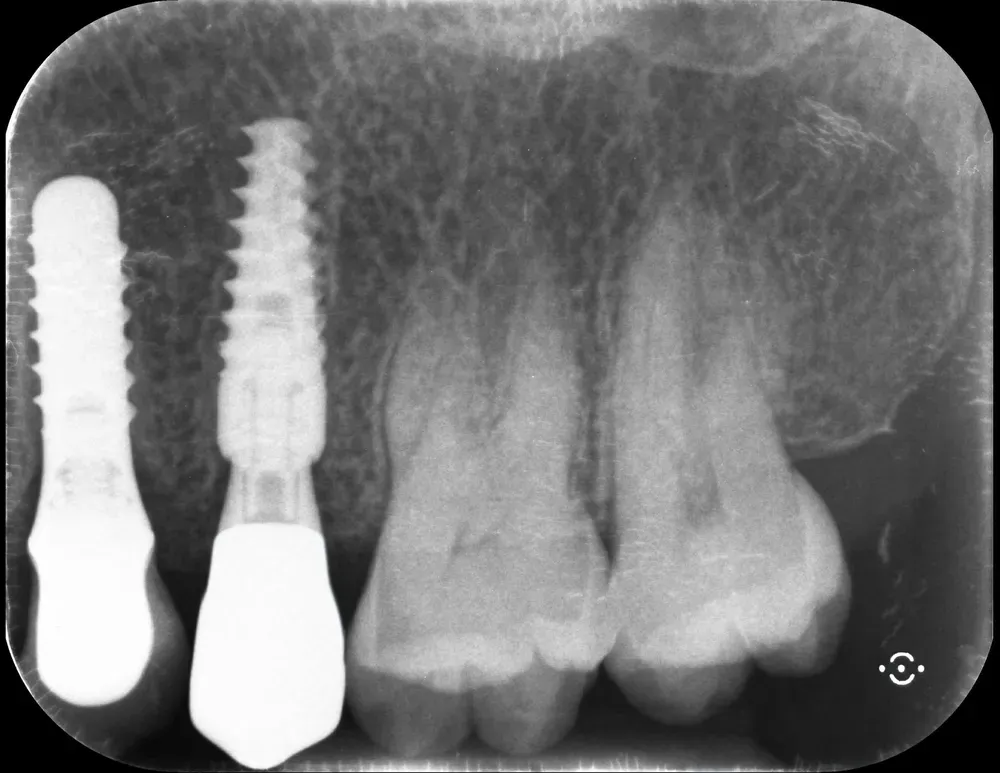

Gli impianti transmucosi devono essere posizionati transmucosi, soprattutto se hanno connessioni non particolarmente “sigillanti”. Usati in tal guisa, sono perfetti. Le immagini che seguono dimostrano che i transmucosi, se posizionati al giusto livello verticale, causano ZERO riassorbimento della cresta ossea.

Non sono fatti per invadere lo spazio biologico. Devono starne fuori.